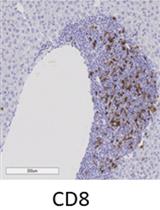

Employing a novel mouse model of immune related adverse events (irAEs) induced by combination of anti-PD1 and anti-CTLA-4 antibodies, we visualized immune infiltration into the liver, lung, pancreas, and colon. Here, we describe the avidin-biotin conjugate (ABC) method used to stain T cells (CD4 and CD8), B cells (CD19), macrophages (F4/80), and cells bound by the in vivo administered rat anti-mouse antibodies for chromogenic immunohistochemistry (IHC). Using a biotinylated goat anti-rat antibody, we detected the localization of cells bound to the in vivo antibodies for PD-1 and CTLA-4. IHC has advantages over other techniques, namely antibody availability, resistance to photobleaching, and greater sensitivity. Additionally, detection and localization of in vivo antibodies can be used in mice models to infer their therapeutic efficacy, stability, and function.Graphical abstract: